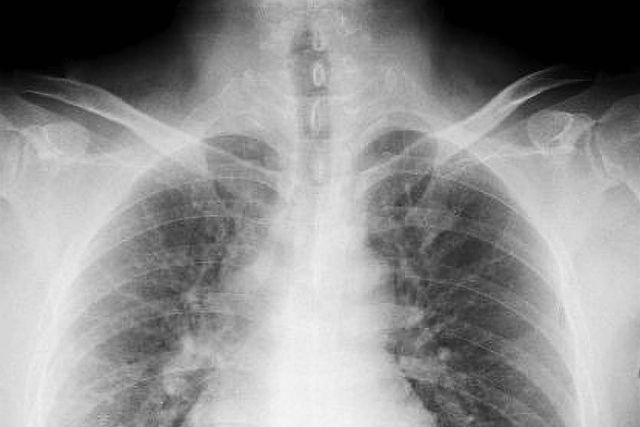

中皮腫と特定するには困難を要することもあり、似た症状のガンや胸膜炎との識別をするには時間がかかることもあります。検査方法は、胸部・腹部のCT検査やエックス線による画像検査を行った上で、細胞診断と病理組織診断が必要となります。治療としては抗がん剤治療、放射線による局所治療を長期的に行っていくことで、回復の可能性が見込めるようになってきました。

咳、吐血の症状が見られることが多く、中皮腫よりも無自覚のまま、CT検査にて判明するケースもあります。腫瘍を切除する外科的手術、放射線による局所治療、薬物療法などの方法が取られますが、発見が遅れて病状が進んでいる場合はそれなりのリスクをともないます。

アスベストを大量に吸い込み過ぎてしまい、肺が綿の繊維質に覆われてしまう「じん肺」という疾患です。肺の機能が損なわれていくため、酸素と二酸化炭素の入れ替えができなくなり呼吸困難を発症します。アスベスト以外にもじん肺の疾患を引き起こす鉱物はありますが、アスベストによって引き起こされたじん肺のことを石綿肺と区別して治療にあたられるのが一般的です。